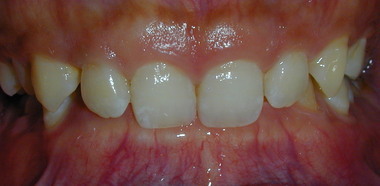

第2期治療(永久歯をきれいに並べる)

第1期治療で顎の土台を整えた後、必要に応じて行います。ワイヤー矯正やマウスピース型矯正装置を使い、歯を一本一本きれいに並べます。